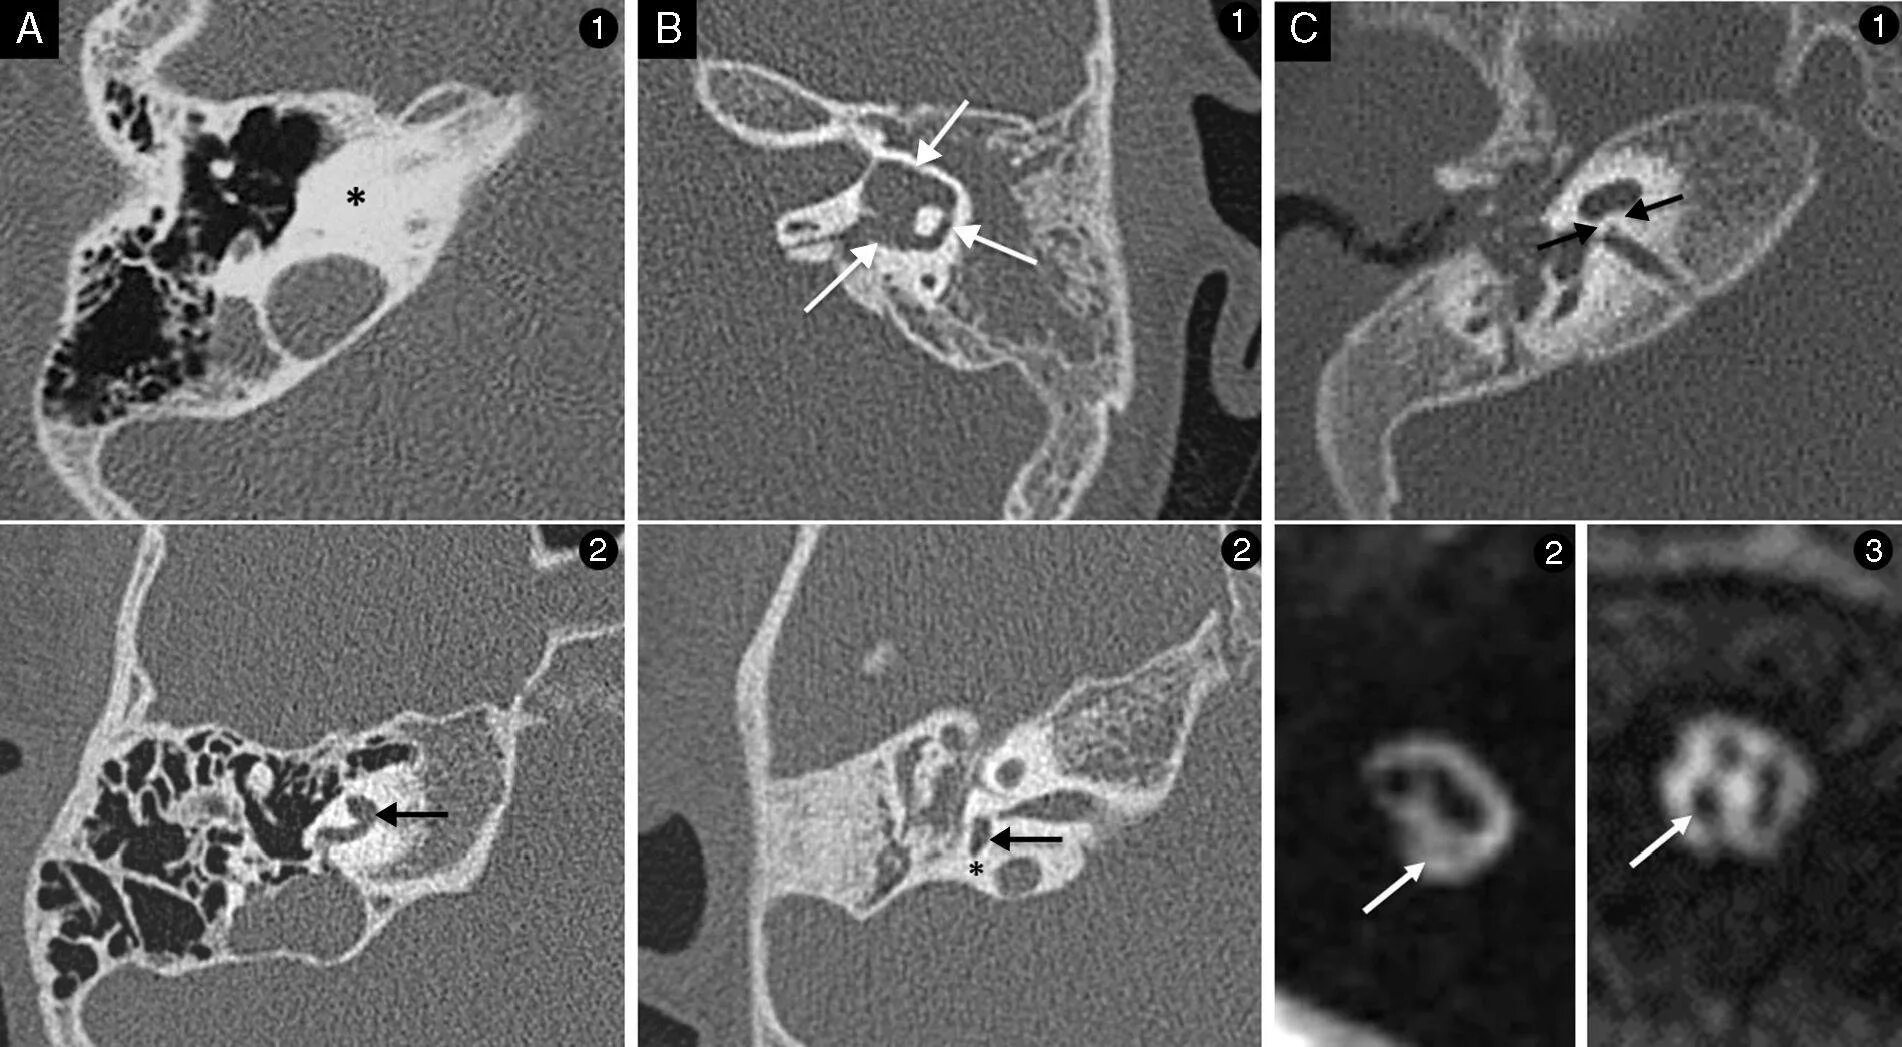

Мрт височных костей в режиме dwi